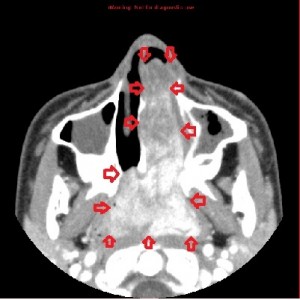

First panel, left to right: Axial contrast-enhanced maxillofacial CT scan in soft-tissue window from superior to inferior, showing a large, avidly enhancing mass in the left nasal fossa, extending posteriorly into the left nasopharnx and crossing into the right nasopharynx behind the nasal septum. Note opacification of the right and left maxillary sinuses, possibly from disturbed drainage.